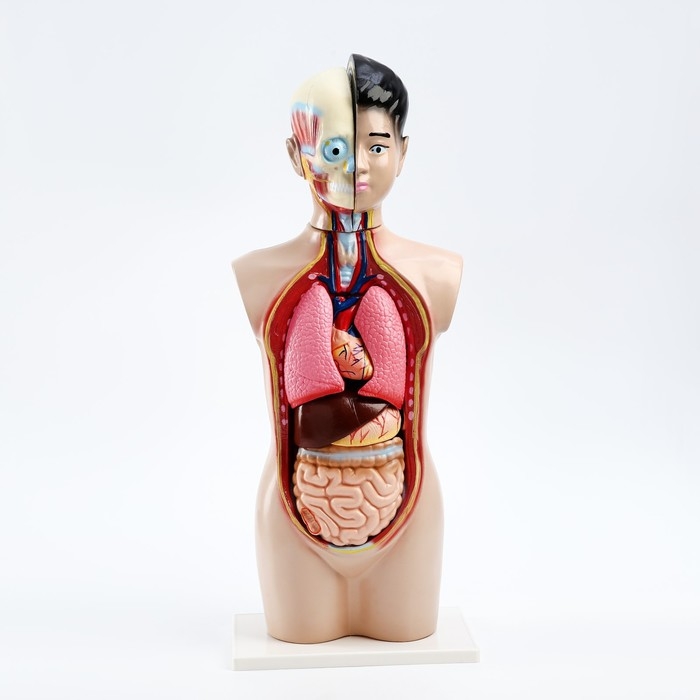

Анатомические модели

ЕКБ 167

No Brand, артикул: 7072352